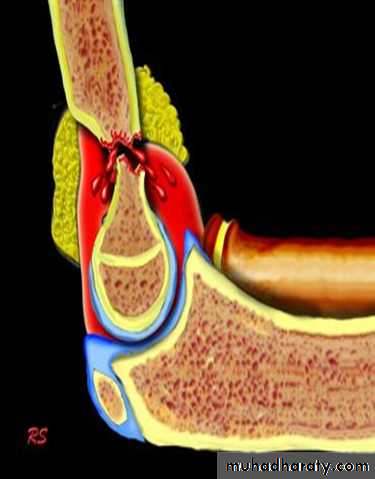

vascular damage : mainly brachial artery

this will lead to ischemia of the forearm (Volkmann's

ischemia ) .

The ischemia also occur in the forearm due to edema in the muscles in close facial space this called( compartment syndrome) , and this will end after 12 hours or less in necrosis of nerves and muscles within the compartment .

Nerves are capable of regeneration but muscles once infarcted can never recover and replaced by inelastic fibrous tissue (Volkmann's ischemic contracture) .

It is a condition in which there is increase in the pressure within the osteofacial space leading to ischaemia and swelling of the muscles within the space ,leading to more decrease in the blood flow in the compartment and if continue more than 12 hours then ischemia and necrosis of the muscles and nerves will be eventual .

This condition can be caused by proximal arterial injury soft tissue bleeding from fractures and operations tight dressing and p.o.p .